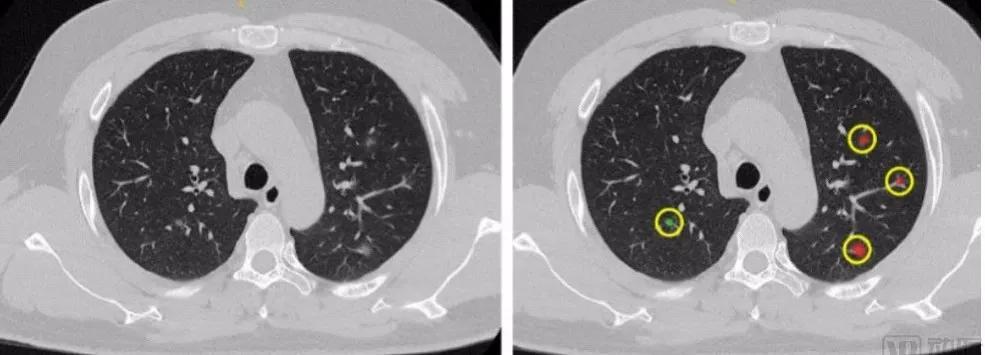

科普下CT影像分析。一个病人的单轮CT在400张左右,医生的工作就是不断比对、审阅几百张影像,找可疑“白点”。

这个过程,不断消耗医生大量的时间成本,高强度工作压力也容易令医生疏忽细小的磨玻璃影。

联影智能的产品,能针对性地识别影像中微小病变,继而自动勾勒生成报告,不放过任何可疑点。

而AI+CT最厉害的地方,要属病灶的观察。过去肉眼很难辨别病灶的变化,但联影的产品能精准检测(90%)、勾画(误差<1%)。